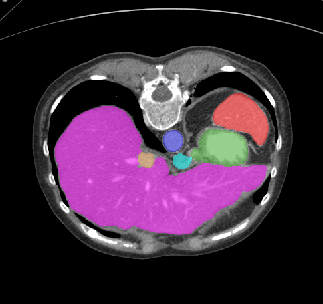

Recently, deep learning methods have achieved state-of-the-art performance in many medical image segmentation tasks. Many of these are based on convolutional neural networks (CNNs). For such methods, the encoder is the key part for global and local information extraction from input images; the extracted features are then passed to the decoder for predicting the segmentations. In contrast, several recent works show a superior performance with the use of transformers, which can better model long-range spatial dependencies and capture low-level details. However, transformer as sole encoder underperforms for some tasks where it cannot efficiently replace the convolution based encoder. In this paper, we propose a model with double encoders for 3D biomedical image segmentation. Our model is a U-shaped CNN augmented with an independent transformer encoder. We fuse the information from the convolutional encoder and the transformer, and pass it to the decoder to obtain the results. We evaluate our methods on three public datasets from three different challenges: BTCV, MoDA and Decathlon. Compared to the state-of-the-art models with and without transformers on each task, our proposed method obtains higher Dice scores across the board.